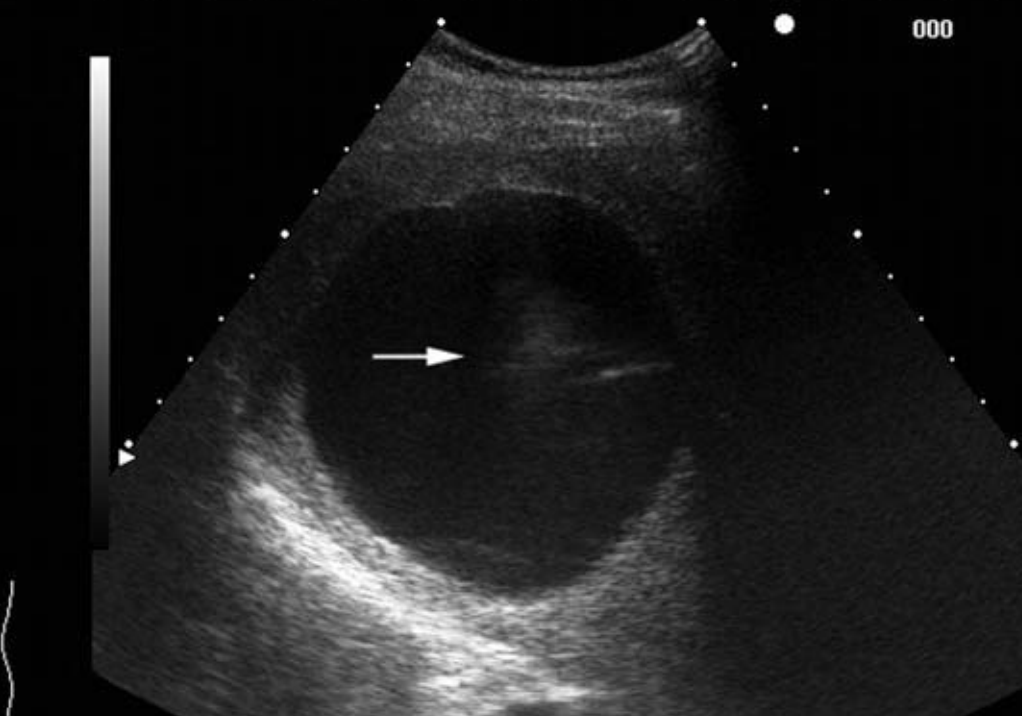

Name the artifact in the image on the left (improved image on the right).

What is the cause of the artifact? How would you (try to) fix it?

Clutter artifact: Acoustic noise arising from side-lobes, grating-lobes, and multipath reverberation. Typically seen in fluid-filled structures.

FIX: spatial compounding, THI